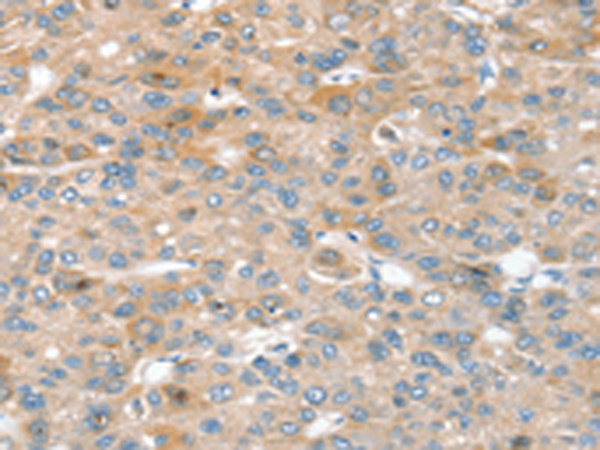

分类: 科研抗体货号: P05302别名:应用: IHC反应种属: Human

分类: 科研抗体货号: P05344别名: SBBI31; MSTP043应用: IHC反应种属: Human, Mouse